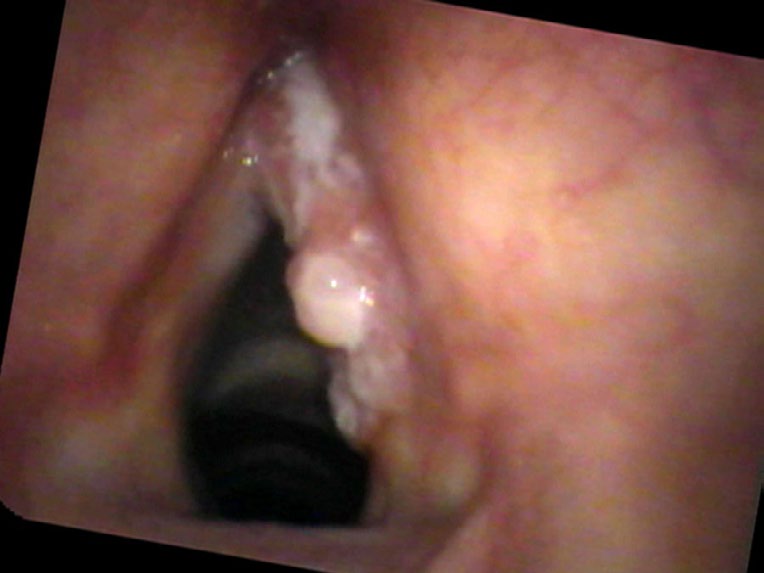

Stefan Kowal developed hoarseness two years ago. He had been seen twice by a laryngologist who told him he had a polyp on the right vocal cord and treated him with antibiotics, reassuring him it wasn’t cancer. His vocal quality fluctuated, such that at times he thought he was improving. Then he definitely became more hoarse. He now cannot yell or even be heard well with any background noise and he develops pain if he speaks very much.

Physicians may over or underestimate the possibility of cancer. Some, who do not want their patients to be concerned, might underestimate the risk of cancer; others bring up the probability of cancer such that surgery seems like the smaller risk than the uncertainty of not knowing. In Mr. Kowal, I was in awe how such a large mass, covering the entire surface of one vocal cord, could be examined two years in a row and still be treated as a polyp. I suspect that equipment played a role, as the flexible fiberoptic scope found in many offices presents a blurry picture. There was no recording made of his prior exams; quite possibly the image in the eyes of the otolaryngologist was fleeting. Couple the problems of no recording and a blurry view with the possibility that the physician did not move the endoscope very close to the vocal cords and the delay in diagnosis is now understandable, even if not desirable.

- Squamous cell carcinoma of the vocal cord often presents with progressive hoarseness, pain with voice use, and an irregular, pebbled surface — but can be mistaken for a polyp without high-quality imaging.